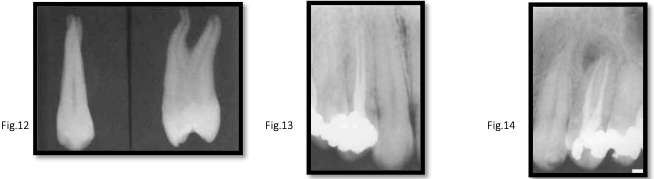

canal anatomy of mx 1st premolar

roots:

62% have 2 roots

38% have 1 root

rarely, 3 roots

canals:

majority (85%) have 2 canals

pulp chamber floor extends into roots, wide bucco-palatal

special cases:

3-rooted premolars are hard to detect radiographically

can have 3 canal orifices: 2 buccal, 1 palatal